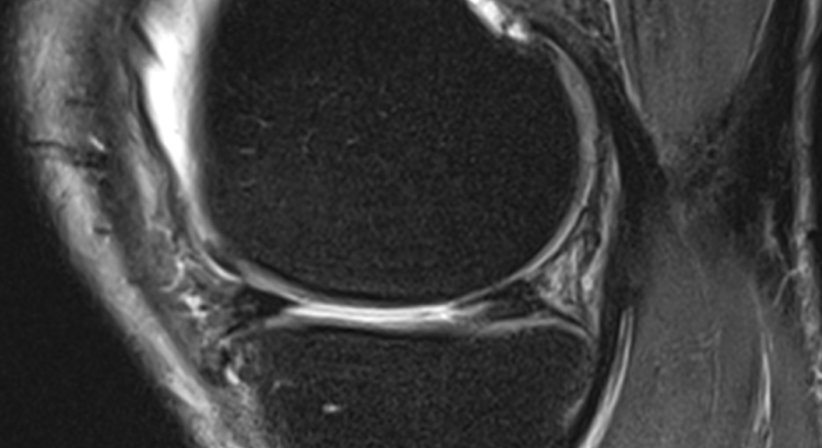

Meniskusschäden sind relativ häufig. Sie entstehen in vielen Fällen aufgrund vorbestehender Abnützungserscheinungen, können aber auch rein traumatisch sein. In der Regel ist der Innenmeniskus häufiger von einem Meniskusschaden betroffen als der Außenmeniskus. Ist der Meniskus nur leicht geschädigt (wie z.B. beim Horizontalriss, der nicht an die Oberfläche heranreicht), kann der Riss konservativ, also ohne Operation, behandelt werden.

Erst wenn ein massiver Riss (z.B. ein sogenannter „Korbhenkel“ (= längsverlaufender Meniskusriss mit Verschiebung abgerissener Meniskusteile in das Gelenk hinein), ein Querriss (vom freien Rand bis zur Basis), ein Lappenriss im Hinter- oder Vorderhorn (= eine Kombination aus Längs- und Querriss), ein Abriss der Meniskusbasis) vorliegt, wird eine Operation notwendig, bei der eine Naht des Meniskus oder die Entfernung des abgerissenen Anteils erfolgt. Ohne einen solchen Eingriff könnte der abgerissene Meniskusteil im Gelenk wie ein Fremdkörper wirken, der den Knorpel in besonderer Weise schädigt und damit zu frühzeitiger Arthrose führt. Der Eingriff erfolgt in Form einer arthroskopischen Operation.